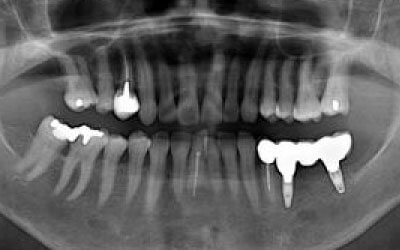

CTを使うことで、骨や歯の状態を3Dで確認でき、正確な距離測定も行えます。

骨の厚さや傾き、神経の位置などを事前にしっかりと計測することで、安全にインプラント治療を行うことができます。